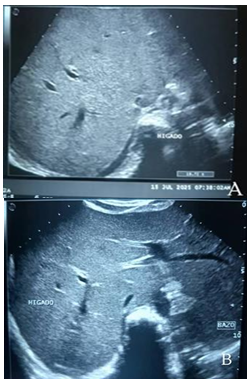

Se trata de adolescente femenino de 12 años de edad cuya madre refiere inicio de enfermedad actual 6 días previo a ingreso presentando fiebre cuantificada en 40 grados centígrados, de difícil manejo asociada a emesis de contenido alimentario en 2 oportunidades posteriormente epigastralgia de moderada intensidad e ictericia (Figura 1).

Figura 1 A. Ictericia en el momento de su ingreso. B. Ictericia durante hospitalización bajo tratamiento. C. Piel normocrómica al egreso